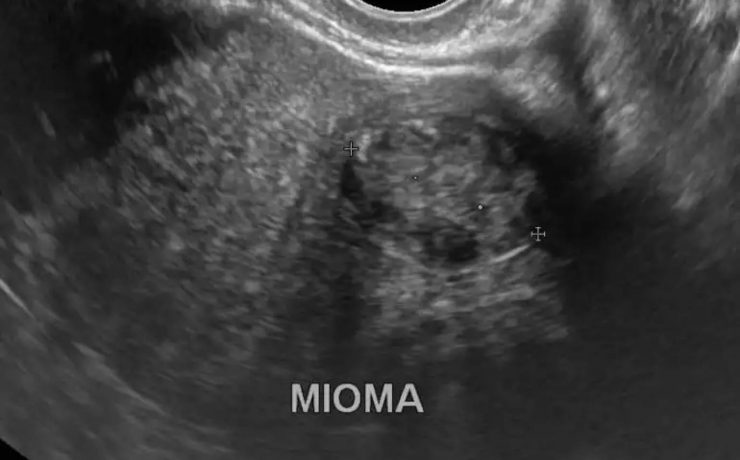

BAZO ACCESORIO SIMULANDO TUMOR SUPRARRENAL

El diagnóstico de los así llamados “incidentalomas” suprarrenales, cada vez más frecuente en la práctica clínica, plantea un diagnóstico diferencial importante. Caso clínico: Se presenta el caso clínico de una paciente de 69 años, hipertensa, con el hallazgo de una masa suprarrenal izquierda aparentemente funcionante, operada por vía laparoscópica y